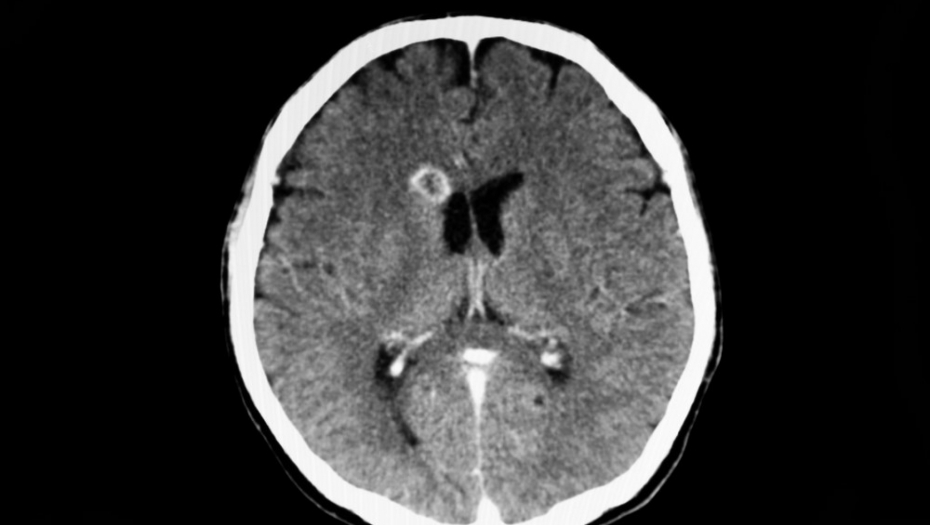

Nakon odrađenog skenera glave lekari su bili sigurni da žena boluje od tumora na mozgu jer su snimci pokazali leziju. Međutim, lumbalna punkcija pokazala je šokantnu dijagnozu - pacijentkinja je bila zaražena Balamuthia mandrillaris, jednoćelijskim organizmom koji se širi na mozak i ubija devet od 10 pacijenata.